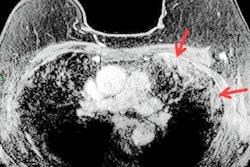

In a normal lung ultrasound scan, the only visible findings are the pleural line and A-lines, which are caused by the reflections of the ultrasound beam. But in a lung scan of a patient with COVID-19, B-lines are also present, as well as subpleural consolidations, a thickened or patchy pleural line, and other structures that can indicate pneumonia and advanced respiratory distress syndrome.